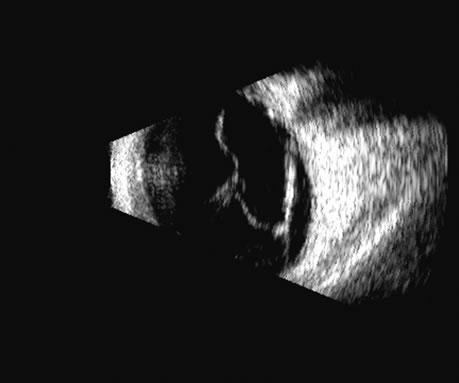

Fig. 16. 3D depiction of a retinal detachment can be helpful in situations in which there is ambiguity among retina, choroid, and schisis. The 3D rotatable display can be perceived from different perspectives, often aiding in the certainty of diagnosis.